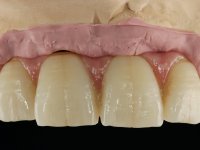

6 meses após a colocação da ponte, o paciente sofre um novo traumatismo comprometendo a viabilidade dos dentes 1.2 e 1.1. Foi realizada uma prótese removível acrílica para reabilitar provisoriamente o paciente enquanto foram extraídos os dentes 1.2 e 1.1 e foi colocado o implante no local do dente 1.1. Passados 3 meses foi realizada uma impressão ao implante colocado no 1.1 e simultaneamente foi feito um arrasto da ponte dos dentes 2.1 e 2.2. Para esse efeito no implante 2.1 foi utilizado um parafuso de uma peça de transferência. Dessa forma conseguiu-se impressionar corretamente a arquitetura gengival do sector antero-superior. O objetivo era simultaneamente impressionar corretamente esta zona e aproveitar a estrutura metálica desta ponte para confecionar a nova ponte de 4 elementos. Foi colocado um parafuso de cicatrização no implante 2.1 e foram acrescentados os dentes 2.1 e 2.2 na prótese removível. Com perícia laboratorial foi criada uma nova infraestrutura metálica de 4 elementos assente nos implantes 1.1 e 2.1 e com os elementos pônticos suspensos 1.2 e 2.2. No implante 2.1 manteve-se a conexão interna ao implante no implante 1.1 optou-se por uma peça intermédia facilitando a inserção da infraestrutura. A nova infraestrutura foi verificada em boca. Como pode ter havido alguma alteração da arquitetura gengival com a remoção da ponte e colocação do parafuso de cicatrização no 2.1, foi feita uma chave de silicone para permitir uma impressão de arrasto da infraestrutura metálica. Uma nova gengiva artificial foi realizada no modelo de trabalho de acordo com esta impressão de arrasto. Foi colocada cerâmica de tonalidade coronária e gengival. A peça protética foi aparafusada lentamente em boca para permitir uma adaptação dos tecidos moles. Após o correto assentamento e verificação imagiológica a ponte foi definitivamente apertada em boca e os orifícios de acesso obturados. Independentemente dos infortúnios que o paciente teve, pude ter a satisfação de o ver contente com esta reabilitação.